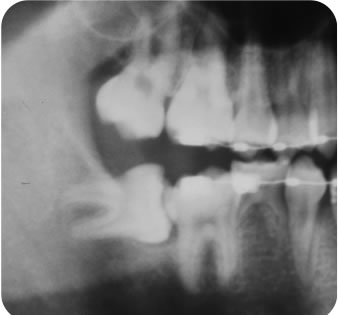

治療例:上顎右側犬歯 完全埋伏

治療例:上顎右側犬歯 完全埋伏

治療前 |

治療後 |